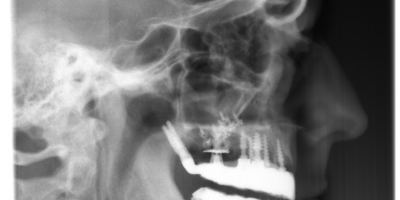

The patient a lady of 72 years broke her bridge in the anterior area.

Treatment option was surgery with ROOTT C (One Piece) and ROOTT P (Pterygoid Implant). The big defect was fulfilled with bone graft material. 2 weeks later a ceramic was placed, cemented and screw retained.